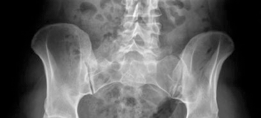

Revision THA Acetabulum Paprosky Type IIIA. ARMD with Metallosis with Severe Periacetabular Osteolysis and Co…

Case Title: Acetabular Impaction Grafting Demographics Age: 78 Sex: female BMI: 28 Relevant Past Medical Hist…